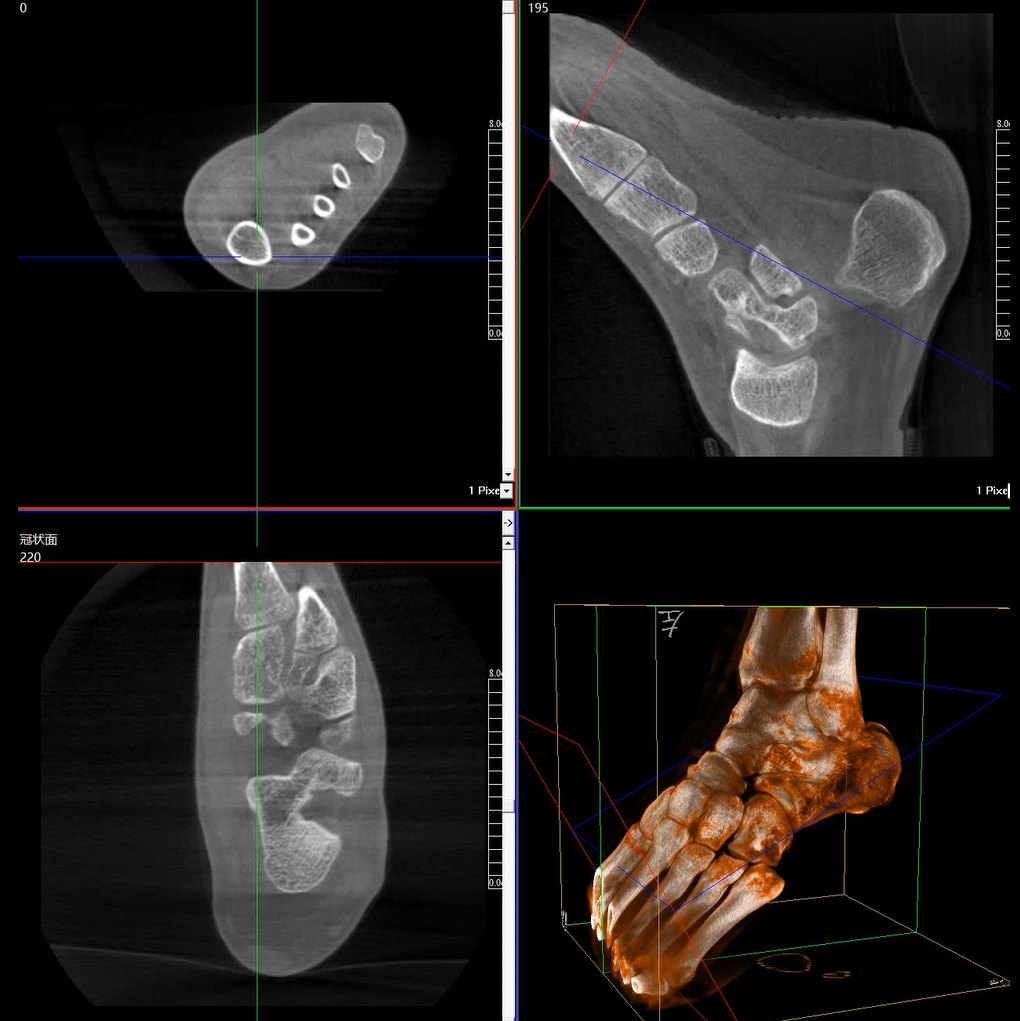

術(shù)中三維成像和橫斷面圖像提供多角度的手術(shù)診斷信息,輔助醫(yī)生進(jìn)行術(shù)中評(píng)估判斷,諸如骨折復(fù)位情況和內(nèi)植入螺釘?shù)某叽绾臀恢?,輔助手術(shù)更好地完成。

提供更大的術(shù)中三維成像視野,采集更多圖像信息,可一次拍全全段頸椎、全段腰椎、七節(jié)胸椎、雙側(cè)骶髂關(guān)節(jié)、股骨頭及單側(cè)盆骨。